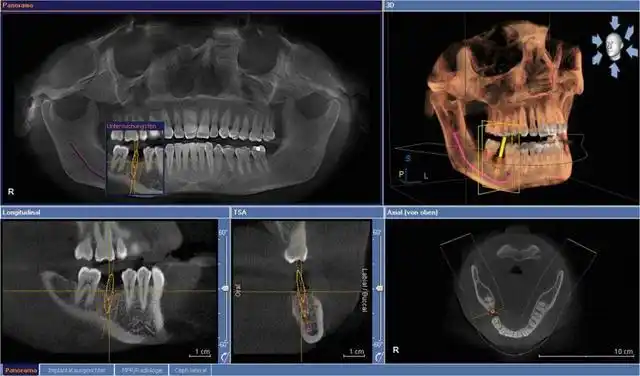

口腔全景片提供的是二维影像,所以它的分辨率不如ct高,而且只能提供一